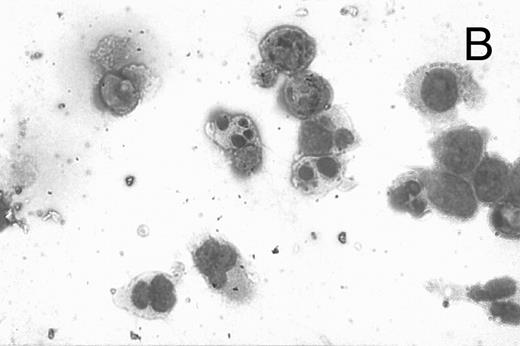

CD437 inhibition of HL-60R growth and induction of apoptosis.Although HL-60R cells are resistant to RA-mediated inhibition of growth,16,17 they are exquisitely sensitive to CD437-mediated inhibition of growth (Fig 1A) with as little as 25 nmol/L CD437 inhibiting growth by approximately 50% (Fig 1B). Similar inhibition of growth was noted in the parental HL-60 cell line (Fig 1C), as well as the RA-resistant K562 leukemia cell line28 (Fig 1D). As evidenced in Fig 1A, there was not only a total inhibition of cellular proliferation in the presence of CD437 but an actual cell loss. We therefore examined whether CD437 induced programmed cell death (apoptosis) in the HL-60R cells. That CD437 indeed induced apoptosis in the HL-60R cells was documented using three independent parameters. (A) HL-60R cells after exposure to 1 μmol/L CD437 displayed marked nuclear fragmentation and chromatin condensation, with the nuclear and cytoplasmic membranes remaining intact (Fig 2), a morphology indicative of apoptosis.29 (B) Incubation of HL-60R cells with 1 μmol/L CD437 resulted in internucleosomal cleavage and laddering of the DNA on gel electrophoresis (Fig 3), a hallmark of apoptosis.29 (C) A number of studies have suggested a critical role for cysteine proteases in the apoptotic process.30-37 Numerous substrates for this family of proteases have now been identified.37-41 PARP, which plays an important role in both DNA synthesis and repair, is cleaved early in the apoptotic process.37 38

CD437-induced apoptosis in HL-60R cells. HL-60R cells were grown as described in the Materials and Methods and exposed to either vehicle alone or CD437 (1 μmol/L) for 24 hours and then stained with aciridine orange. (A) Cells exposed to only vehicle. (B) Cells exposed to CD437 (1 μmol/L).

A number of antagonists and promoters of apoptosis have recently been described. The bcl-2 family, which now consists of 7 different proteins encoded by 7 different genes, has now been characterized (Vaux and Strasser37 and the references contained within). Bcl-2 and bcl-XL are expressed in numerous cell types and are potent antagonists of apoptosis. We were unable to detect bcl-XL expression in HL-60R or HL-60 cells as has previously been described,43 but found that bcl-2 is highly expressed in these cells and is also cleaved during CD437-mediated apoptosis (Fig 6). Phosphorylation of bcl-2 has been previously described as a mechanism for bcl-2 inactivation during the apoptotic process.44 Whether cleavage of bcl-2 represents another mechanism by which bcl-2 is inactivated remains to be determined. That this cleavage of PARP, CPP32, and bcl-2 does not simply represent random cleavage of a number of proteins is suggested by our inability to detect cleavage of lamin B (data not shown), which is often found cleaved in a variety of forms of programmed cell death.39 41 CD437 also markedly inhibited growth of the K562 cells (Fig 1C) but contrary to HL-60R cells apoptosis was not noted until 144 hours of exposure to CD437, as indicated by internucleosomal degradation demonstrated by gel electrophoresis (Fig 7). We also examined the ability of CD437 to induce PARP cleavage and apoptosis in primary leukemic blasts obtained from a patient with acute myelogenous leukemia. As shown in Fig 8C, enhanced PARP cleavage was noted within 24 hours after exposure to 1 μmol/L CD437, with the apoptotic morphology noted at 48 hours of exposure (Fig 8A and B).

CD437-mediated apoptosis in primary leukemia cells. Leukemic blasts were isolated as described in the Materials and Methods. Cells were exposed to 1 μmol/L CD437 for various periods of time and PARP cleavage was assessed as previously described. (A) Leukemic cells exposed only to vehicle for 48 hours. (B) Leukemic cells exposed to 1 μmol/L CD437 for 48 hours. (C) CD437-mediated PARP cleavage. Lanes 1 and 3, cells exposed to vehicle only for 24 and 48 hours, respectively. Lanes 2 and 4, cells exposed to 1 μmol/L CD437 for 24 and 48 hours, respectively.